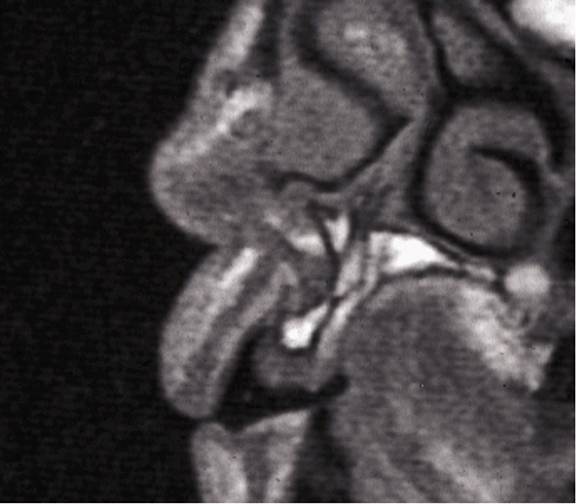

Above: A sectional MRI of the upper incisor area showing loss of horizontal bone requiring grafting.